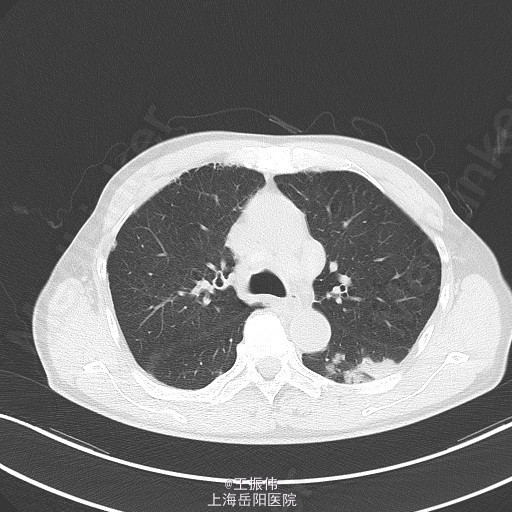

主诉、病史:老年男性,咳嗽咳痰15天,患者15日前因受凉后出现咳嗽,咳黄脓痰,自觉有发热,未测体温,6月25日至我院查血常规:白细胞:7.7*10^9/L,血红蛋白:106g/L,血小板:149*10^9/L,中性粒细胞:68.7,胸部CT:右肺上叶占位灶,两肺小结节灶,纵膈淋巴结增大,左肺下叶、右肺中叶炎症;两肺气肿伴肺大泡。自服止咳中成药(具体不详)后无明显好转。6月27日至地段医院就诊,予头孢羟氨苄片、金荞麦片、强力枇杷露,未见明显好转。

气管居中,颈静脉正常,胸廓两侧对称,无桶状胸,呼吸运动两侧对称,呼吸频率20次/分,肋间隙正常,无胸膜摩擦感。两肺叩诊清音,右肺可闻及湿性啰音,胸部CT:右肺上叶占位灶,两肺小结节灶,纵膈淋巴结增大,左肺下叶、右肺中叶炎症;两肺气肿伴肺大泡。组织病理【z155818】:灰白组织2粒,直径0.1cm。诊断:(左肺下叶开口)肉芽肿性炎,结核可能,请临床做相关病原体检测。支气管镜痰涂片:找到抗酸杆菌。